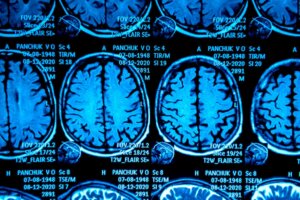

Una maggiore comprensione della malattia e apparecchiature più sofisticate hanno reso possibile la diagnosi anche attraverso la diagnostica per immagini. È noto, in questo senso, che attraverso l’imaging possono essere individuati alterazioni nella lunghezza del bulbo oculare, alterazioni della testa del nervo ottico e suo aumento di tortuosità e sindrome della sella turcica vuota, tra le altre cose.

A tale scopo lo specialista può eseguire anche una venografia RM e scansioni TC. Come complemento, verranno eseguiti esami del sangue e persino la puntura lombare; in parte per escludere una diagnosi differenziale. Il medico deve seguire un preciso protocollo diagnostico poiché i sintomi sono molto generali.